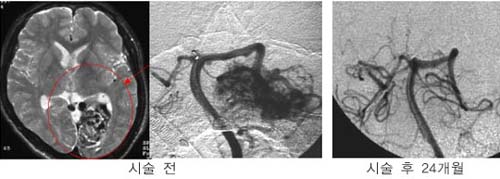

³úµ¿Á¤¸Æ

񃀁

³ú

±íÀº °÷¿¡ À§Ä¡ÇÏ¿© ³úÃâÇ÷À» ÀÏÀ¸Å² 17¼¼

¿©ÀÚȯÀÚÀÇ MRI ¹× ³úÇ÷°üÃÔ¿µ¼ú »çÁø.

³úÀÇ

±íÀº °÷¿¡ ³úµ¿Á¤¸Æ±âÇüÀÌ À§Ä¡ÇÏ¿© ¼ö¼úÀû

Ä¡·á°¡ ºÒ°¡´ÉÇÏ¿´À¸³ª °¨¸¶³ªÀÌÇÁ ½Ã¼ú

ÈÄ 24°³¿ù°¿¡ ¸ðµÎ ¿ÏÄ¡µÇ¾ú´Ù

°æ·ÃÀ»

ÁÖ¼Ò·Î ÀÔ¿øÇÑ È¯ÀÚÀÇ MRI ¹× ³úÇ÷°üÃÔ¿µ¼ú

»çÁø.

µ¿Á¤¸Æ±âÇüÀÇ

Å©±â°¡ Ä¿¼ ¼ö¼úÀÇ À§Ç輺ÀÌ ³ô¾Æ °¨¸¶³ªÀÌÇÁ¸¦

°èȹÇÏ¿´´Ù. º´º¯ÀÇ Å©±â°¡ Ä¿¼ °¨¸¶³ªÀÌÇÁ

¹æ»ç¼±¼ö¼úÀ» ¸îÂ÷·Ê¿¡ ³ª´©¾î¼ ½ÃÇàÇÏ·Á

ÇÏ¿´À¸³ª ÇÑÂ÷·ÊÀÇ °¨¸¶³ªÀÌÇÁ ½Ã¼ú ÈÄ

24°³¿ù° ¸ðµÎ ¿ÏÄ¡µÇ¾ú´Ù.

º´º¯ÀÇ

Å©±â°¡ Å« µ¿Á¤¸Æ±âÇüÀÇ °æ¿ì °¨¸¶³ªÀÌÇÁ

¹æ»ç¼±¼ö¼úÀ» ¸îÂ÷·Ê¿¡ ³ª´©¾î¼ ½ÃÇàÇÏ¿©¾ß

Çϳª ÀϺΠȯÀÚÀÇ °æ¿ì ÇÑÂ÷·ÊÀÇ °¨¸¶³ªÀÌÇÁ

½Ã¼ú·Îµµ ¿ÏÄ¡¸¦ º¸¿´´Ù